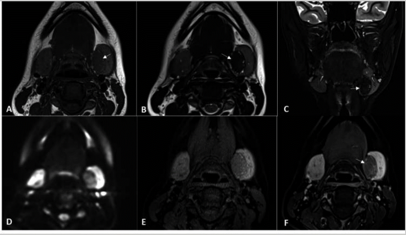

In this study, we aim to initiate the development of Radiology Foundation Model, termed as RadFM.We consider the construction of foundational models from the perspectives of data, model design, and evaluation thoroughly. Our contribution can be concluded as follows: (i), we construct a large-scale Medical Multi-modal Dataset, MedMD, consisting of 16M 2D and 3D medical scans. To the best of our knowledge, this is the first multi-modal dataset containing 3D medical scans. (ii), We propose an architecture that enables visually conditioned generative pre-training, allowing for the integration of text input interleaved with 2D or 3D medical scans to generate response for diverse radiologic tasks. The model was initially pre-trained on MedMD and subsequently domain-specific fine-tuned on RadMD, a radiologic cleaned version of MedMD, containing 3M radiologic visual-language pairs. (iii), we propose a new evaluation benchmark that comprises five tasks, aiming to comprehensively assess the capability of foundation models in handling practical clinical problems. Our experimental results confirm that RadFM significantly outperforms existing multi-modal foundation models. The codes, data, and model checkpoint will all be made publicly available to promote further research and development in the field.